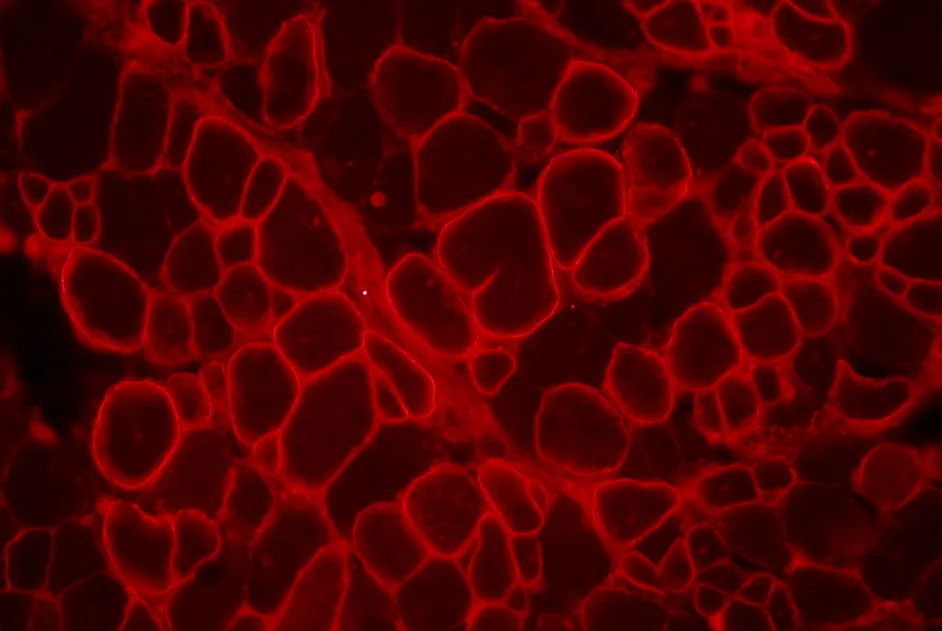

Mise au point d’une technique de diagnostic de la myopathie facio-scapulo-humérale (FSH) plus précise et plus sensible : le peignage moléculaire